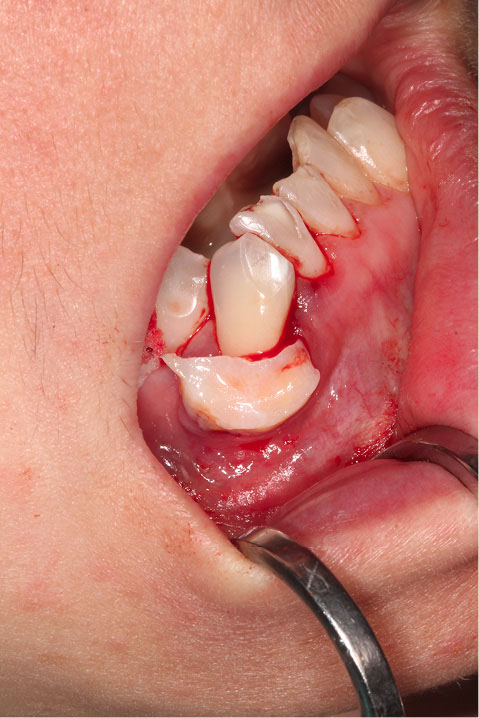

Figure 2 shows the final tunnel preparation before the placement of CTG. Figure 3 shows the harvested CTG positioned on the exposed root surface to check its dimensions before placement inside the tunnel on the buccal aspect of tooth #43. Figure 4 shows suturing after the CTG has been positioned inside the tunnel. Please note that the sutures were kept longer than usual to prevent the poking of the suture ends into the lower lip and buccal mucosa. Figure 5 shows the postoperative condition at five-week interval.

japid-12-90-g002

Figure 2. Final tunnel preparation prior to the placement of CTG The harvested CTG positioned on the exposed root surface to check its dimensions prior to placement.